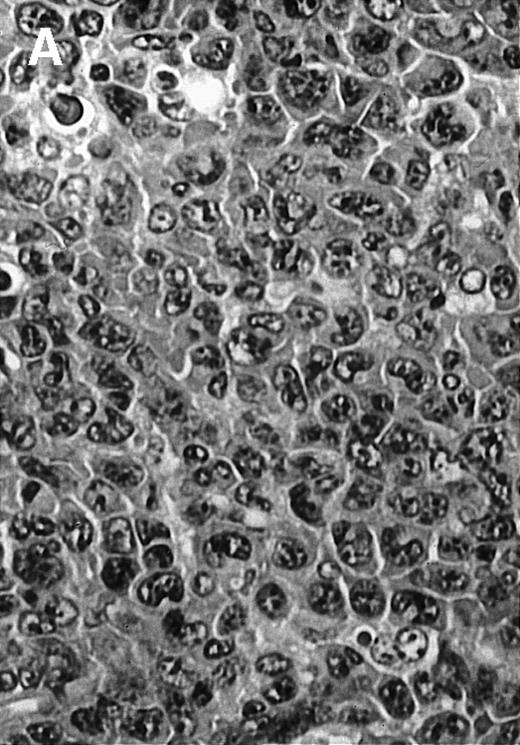

To analyze expression of the human CD40L protein in murine tissues, samples from the small intestine, colon, liver, and spleen were analyzed by HE staining as well as immunohistochemistry. We found that in mice immunized with ST40L, the Peyer's patches were prominent (Figure 1A), and the majority of cells in the Peyer's patches could be seen to express the human CD40L protein (positive: brown or yellow color; negative: blue color) (Figure 1B). There were a few CD40L+ cells in spleen, but not in liver. In contrast, human CD40L was not detectable in the Peyer's patches of mice treated with ST (Figure 1C). To further confirm the secretion of human soluble CD40L by transfected murine cells into the sera, we next examined it by ELISA (Figure 2). Human soluble CD40L protein was detectable only in BALB/c mice treated with ST40L with or without administration of BCL cells, but not detectable in mice treated with ST and/or BCL cells. The level of soluble CD40L protein in the sera peaked at 1 week after oral administration and was detectable until 7 to 8 weeks.

Presence of transduced human CD40L protein in mice treated with ST40L.

(A) HE staining of intestine ( × 100) of BALB/c mice killed 1 week after oral administration of ST40L. (B) Immunostaining of Peyer's patches using antihuman CD40L Ab (×400) of BALB/c mice killed 1 week after oral administration of ST40L. (C) Immunostaining of Peyer's patches using antihuman CD40L Ab (×400) of BALB/c mice killed 1 week after oral administration of ST.

To explore the mechanisms of the protection from BCL growth, histologic analysis was performed on tumor tissue from mice treated with ST40L, ST, or PBS alone. In the mice treated with PBS alone, no cellular infiltrate expressing FasL was observed in the surrounding tissues and inside the BCL region (Figure 4A and D). In contrast, infiltrating lymphocytes expressing FasL were observed around the vessels and also scattered in the smaller tumor tissues in the mice treated with ST (Figure 4B and E). Small hard nodules (2-5 mm in diameter) were observed at the SC injection sites of the long-term survival mice that had been treated with ST40L. On histologic analysis, these small nodules were confirmed to be the result of an accumulation of lymphocytes, and not BCL cells (Figure 4C). These lymphocytes were also found to be strongly positive for FasL expression (Figure 4F). On the other hand, lymphocytes infiltrating in the nodules were stained by either CD4+ Ab or CD8+ Ab, but the ratio of CD4+ and CD8+ cells was not 1-sided (data not shown).

Histologic analysis of A20 tumors excised 21 days postchallenge from BALB/c mice immunized with ST40L.

(A) HE stain of a BCL region in a mouse treated with PBS alone. (B) HE stain of a smaller BCL region in a mouse treated with ST. (C) HE stain of a small hard nodule at the SC injection site in a mouse treated with ST40L. (D) Fas ligand staining of a BCL region in a mouse treated with PBS alone. (E) Fas ligand staining of a BCL region in a mouse treated with ST. (F) Fas ligand staining of a small hard nodule at the SC injection site in a mouse treated with ST40L. Original magnifications are ×400.